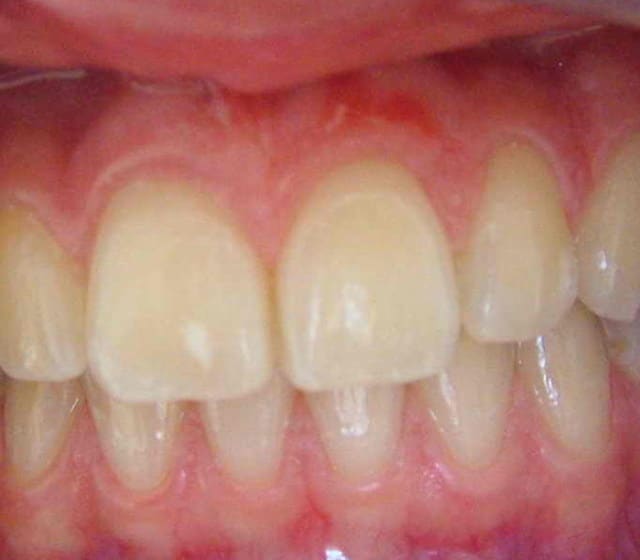

Voilà, je viens de reprendre 2 clichés plus nets.

Merci pour les réponses.

Au collet de 21 ce n'est pas du pus mais un petit morceau de composite flow .( que je me suis empressé d'enlever après la photo).

c'est curieux, ça ressemble à un site greffé par conjonctif enfoui avec deux décharges.

tt de paro anterieur???mais de toute facon ca ne doit pas partir seul